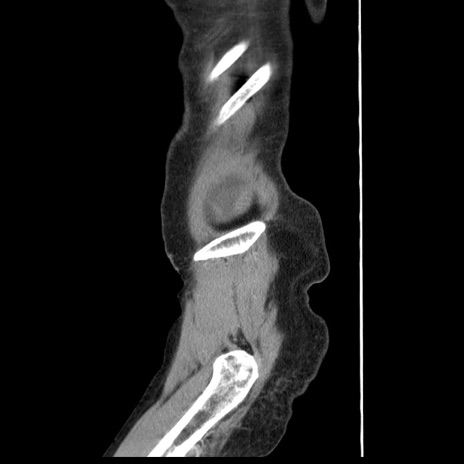

横断像

冠状断像